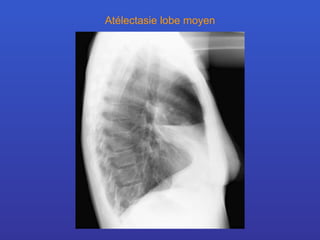

Atélectasie lobe moyen